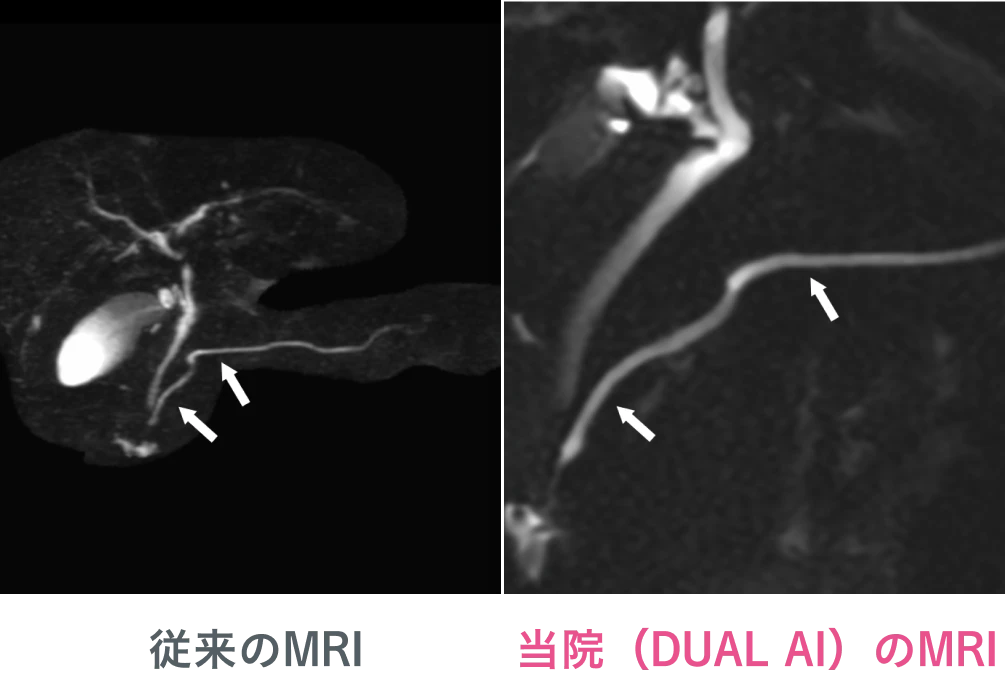

MRCP(MR胆管膵管撮影)での比較

従来よりはるかに拡大して膵管を鮮明に出すことができ、微小膵癌の発見に貢献します。